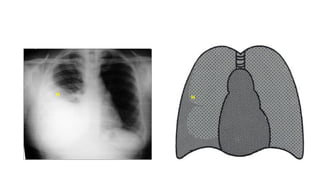

The document presents a chest X-ray examination summary by Ninian Peckitt, detailing various respiratory conditions including tracheal deviation, pleural effusions, and lung collapses. Findings suggest thoracic trauma and hyperinflation in the lungs. Additionally, it includes links to medical products and their pricing.